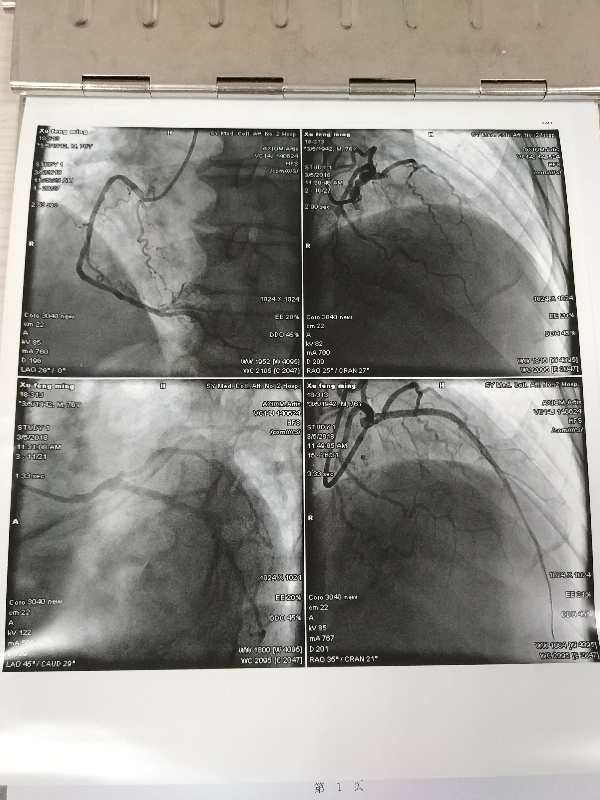

抽血、用药、备皮、签署文书及交代病情、导管室备战的一切事宜,几乎同时进行。为患者紧急做了冠脉造影:前降支近端完全闭塞,无侧支循环,这种病变随时威胁生命,因此开通时间是患者生命的关键。

不负众望,紧迫的赛跑中顺利的开通了闭塞血管。患者转危为安。这是一场无烟战事:患者到院大门时间:10:52,球囊扩张、闭塞血管开通时间:11:43,D to B时间:51分钟!